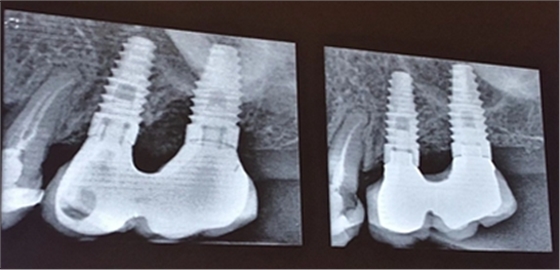

手術(shù)方式治療則需通過翻瓣清潔種植體及修復體上菌斑牙石,推薦在此過程中使用士卓曼鈦刷,因為該鈦刷不會損傷種植體表面細微結(jié)構(gòu)。之后進行植骨蓋膜來促進種植體周圍吸收部分的骨的重建。